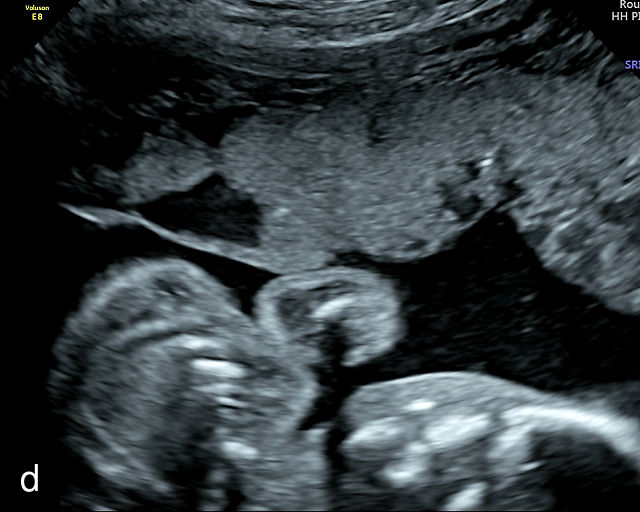

Circumvallate placenta

A circumvallate placenta is one in which the chorionic plate (the fetal surface of the placenta) is smaller than the basal plate, resulting in placental tissue extending beyond the margins of the membrane insertion.9 This creates rolled edges with a cuplike appearance. Rather than inserting at the edges of the placenta, the membranes insert into the fetal surface. In a review of 16 042 placental pathology reports collected over 13 years, Stuijt et al. found that circumvallate placentas were present in 2.2% of cases.159 Circumvallate placentas have been associated with an increased risk of adverse pregnancy outcomes, including FGR, placental abruption, preterm birth and fetal demise.160,161

Sonographically, a circumvallate placenta appears as a placenta with raised, rolled edges, which can be identified on grayscale ultrasound (Figure 13). Additionally, a placental shelf or band may be observed at the placental margin. The differential diagnosis includes amniotic bands, uterine synechiae and uterine septa. However, achieving an accurate prenatal diagnosis can be challenging. An early study by Harris et al. found a poor correlation between the sonographic diagnosis of circumvallate placenta and confirmation on placental examination after delivery.162 In that study, placental sonograms reviewed by expert sonologists showed that 17 of 49 normal placentas were incorrectly diagnosed as probably or definitely circumvallate by one or more observers. Conversely, in a study of 10 patients in which prenatal ultrasound had revealed raised rolled placental edges thought to represent circumvallate placenta, the diagnosis was confirmed on gross placental examination in eight cases.163 This high false-positive rate poses a significant challenge in prenatal ultrasound diagnosis and impacts the interpretation of reported outcomes. The difficulty in achieving an accurate diagnosis likely contributes to the wide range of reported prevalence of circumvallate placenta.

13

(a–e) Grayscale images of circumvallate placentas showing the rolled edges of the placentas.

Recent evidence provides additional insight into the clinical significance of this condition. A retrospective cohort study by Herrera et al. examined 179 patients with a prenatal diagnosis of circumvallate placenta at an average of 19.8 weeks.164 The study found no correlation between a circumvallate placenta and adverse pregnancy outcome. These authors suggested that no additional surveillance was necessary when a circumvallate placenta is suspected on prenatal ultrasound. This difference in reported outcomes may reflect the false-positive diagnoses of circumvallate placenta in sonographic studies.

When findings consistent with a circumvallate placenta are observed on prenatal ultrasound, efforts should focus on achieving an accurate diagnosis. The use of three-dimensional ultrasound may improve diagnostic accuracy.9,165,166 If a circumvallate placenta is confirmed or strongly suspected, serial growth scans and consideration of antepartum fetal surveillance in the late third trimester are prudent to monitor for potential complications.